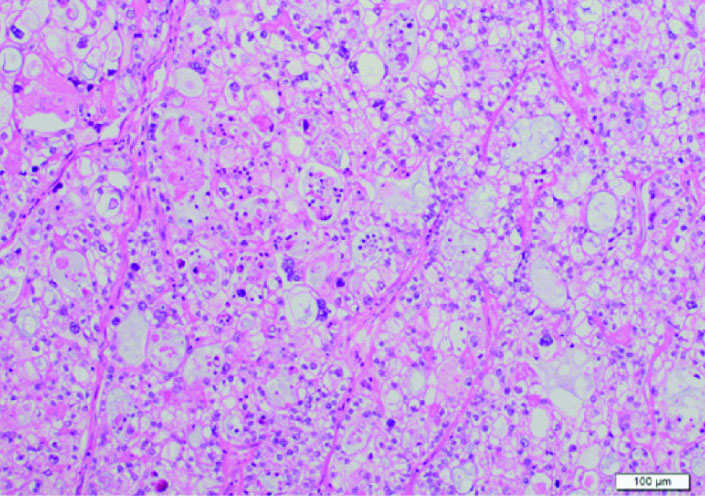

According to histopathological examinations (Fig. 1), atypical cells with clear cytoplasm and anisonucleosis were growing hyperplastically in sheet-like and cystic structures. The patient was diagnosed with clear cell adenocarcinoma. Atypical cells were partially positive for PTHrP (Fig. 2A) and positive for G-CSF (Fig. 2B). The case was considered to be clear cell carcinoma producing PTHrP and G-CSF. The patient had negative peritoneal cytology and was staged pT1a.

![]() Click for large image | Figure 1. Histological examination. Atypical cells with clear cytoplasm and anisonucleosis were growing hyperplastically in sheet-like and cystic structures. Its finding is identical to clear cell carcinoma. |